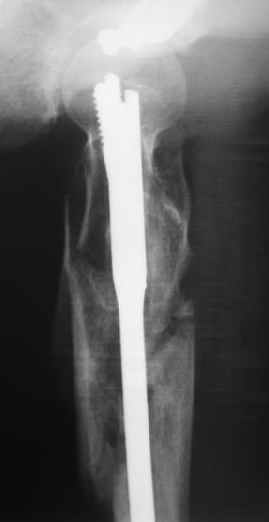

Другое наблюдение:Мужчина, 1957 г.р. Травма в результате ДТП 12.09.04г.

Диагноз: Закрытый оскольчатый подвертельный перелом правой бедренной кости со смещением отломков, оскольчатый перелом большого вертела, отрывной перелом малого вертела.Сопутствующие заболевания: Язвенная болезнь желудка, ремиссия.

Наверно, можно и так сказать, но можно и тоже самое - 4-фрагментный вертельный перелом. Выбор тот же, но с учетом молодого возраста реконструкционный гвоздь тут более применим. Вот уже наш пример.